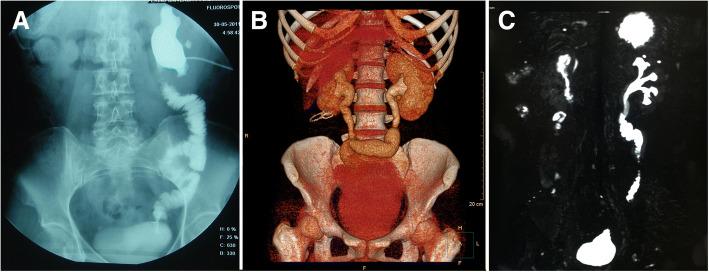

回肠代输尿管术的技术考量与结果:一项中国的回顾性研究

Technical considerations and outcomes for ileal ureter replacement: a retrospective study in China.

Ileal ureter replacement is an alternative treatment for various length ureter defects. We present our experience and outcome of ileal ureter replacement in China.

There were 23 patients who underwent ileal ureter replacement by the same surgeon. Twenty patients were performed unilateral ileal ureter replacement, two patients underwent a combination of ileal ureter replacement and Boari flap-psoas hitch, and one received bilateral ileal ureter replacement. Among these patients, the main cause leading to surgical treatment was iatrogenic injuries (n = 15), especially urinary surgery procedure (n = 11). The median follow-up time was 45 months. There were 6 early complications and 6 late complications after operation. Only one patient suffered from small bowel-related complication and was cured by conservative treatment. Only the patient who underwent bilateral ileal ureter replacement had metabolic acidosis. And 22 patients (95.7%) had a good renal function.

CONCLUSIONS